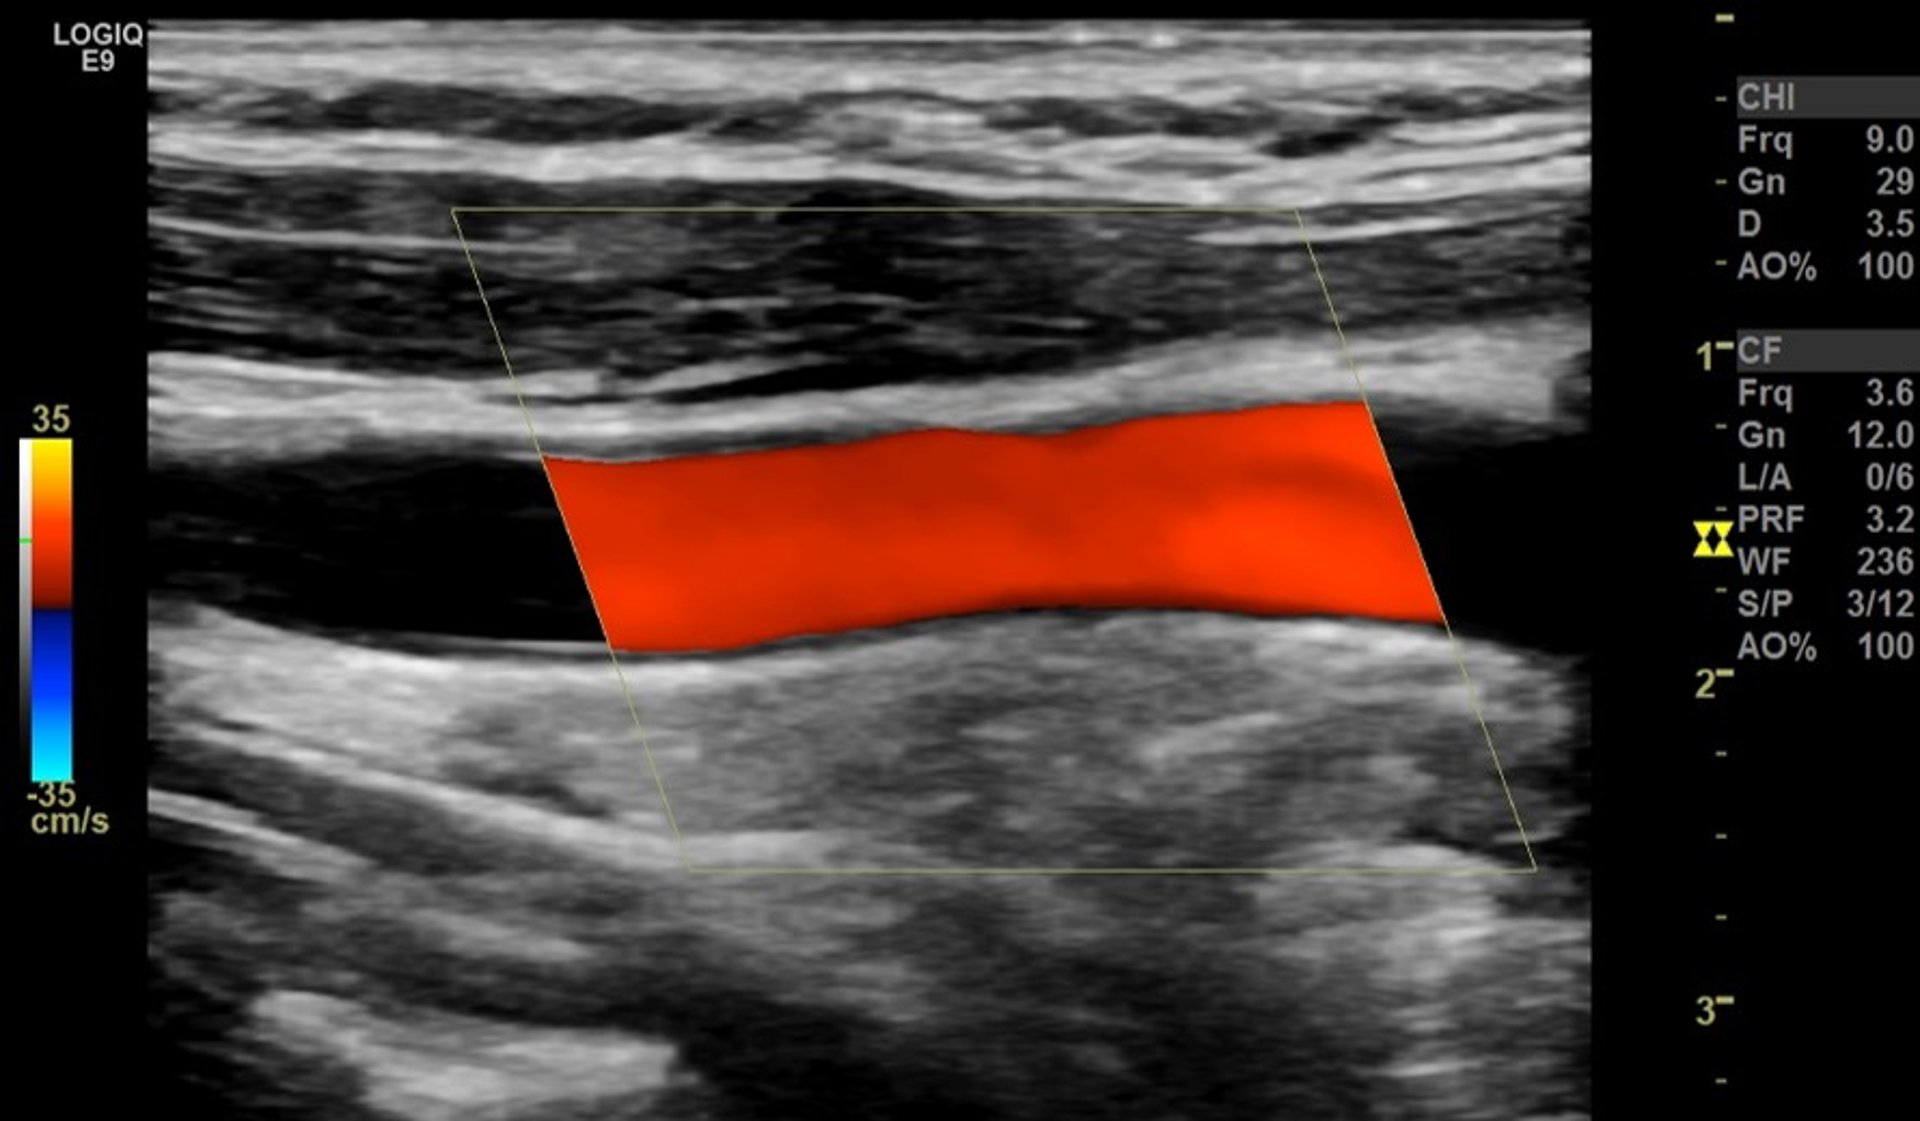

頸動脈のカラードプラ超音波検査

赤色の縞は、側面から見た首の太い動脈(総頸動脈)を通る血流が正常で閉塞していない状態を示しています。

Image provided by Mustafa Mafraji MD